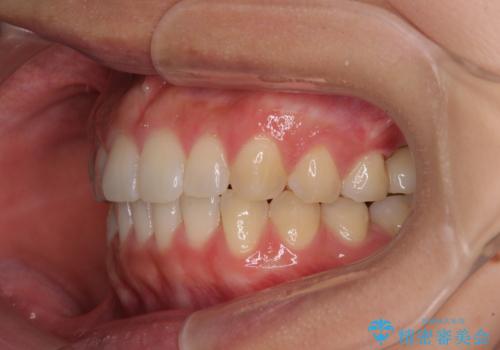

インプラントによる補綴治療とインビザライン矯正

- 抜歯が必要と診断された奥歯を気にして来院された患者様です。

抜歯の上インプラントによる補綴治療を行うこととなりましたが、前歯の叢生も気になるとのことで並行して矯正治療を行うこととしました。

歯列不正は軽微であったので、インビザラインによる矯正治療とし、矯正治療中にインプラント埋入を行う予定としました。

痛みがないので、ボロボロのまま放置していましたが、抜歯後は汚れが溜まりにくくなりスッキリとしたようです。

前歯のデコボコも解消され、ブラッシングが楽になりました。